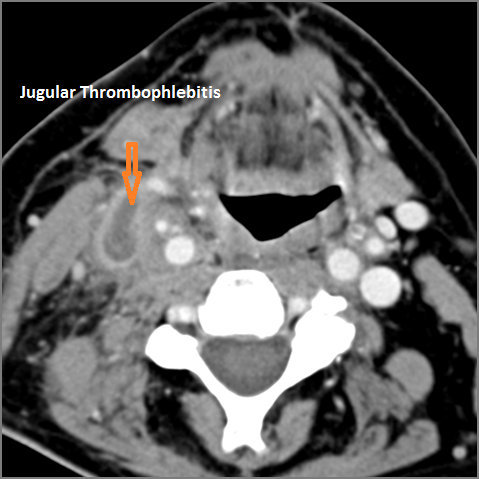

Vascular Findings

There is evidence of thrombus, thrombophlebitis or other occlusive or inflammatory process of the jugular vein or smaller jugular venous tributaries. [Yes/No]